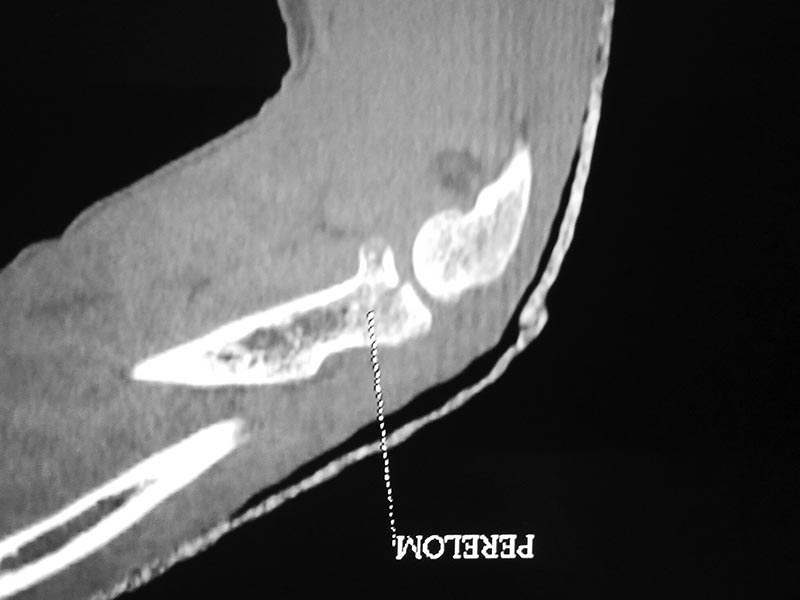

Судя по 3-Д КТ, перелом - много оскольчатый, но без смещения.

Один снимок всего? Может КТ-срезы какие-нибудь есть, R-снимки без гипса фас/профиль? По этому снимку вроде бы и нет вдавленного перелома. Суставная поверхность расколота - это да, но импрессии не увидел. Мы бы попытались сохранить головку.

Синтезировать, или вообще не трогать. А 3D картинки дают мало информации. Лучше представляйте срезы в 3-х плоскостях.

На представленных снимках есть смещение суставной поверхности. Принцип лечения внутрисуставных переломов - восстановление суставной поверхности. У нас есть опыт восстановления таких переломов микровинтами. Удачи!

Для выработки показаний достаточным бывают стандартные снимки, но иногда требуется косая рентгенограмма по Coyle. И для подтверждения смещений и оценки внутрисуставных фрагментов рекомендуется КТ, а 3D снимки показывают только поверхность, т.е. получается общая картина. МРТ дает возможность оценить состоянии связок.